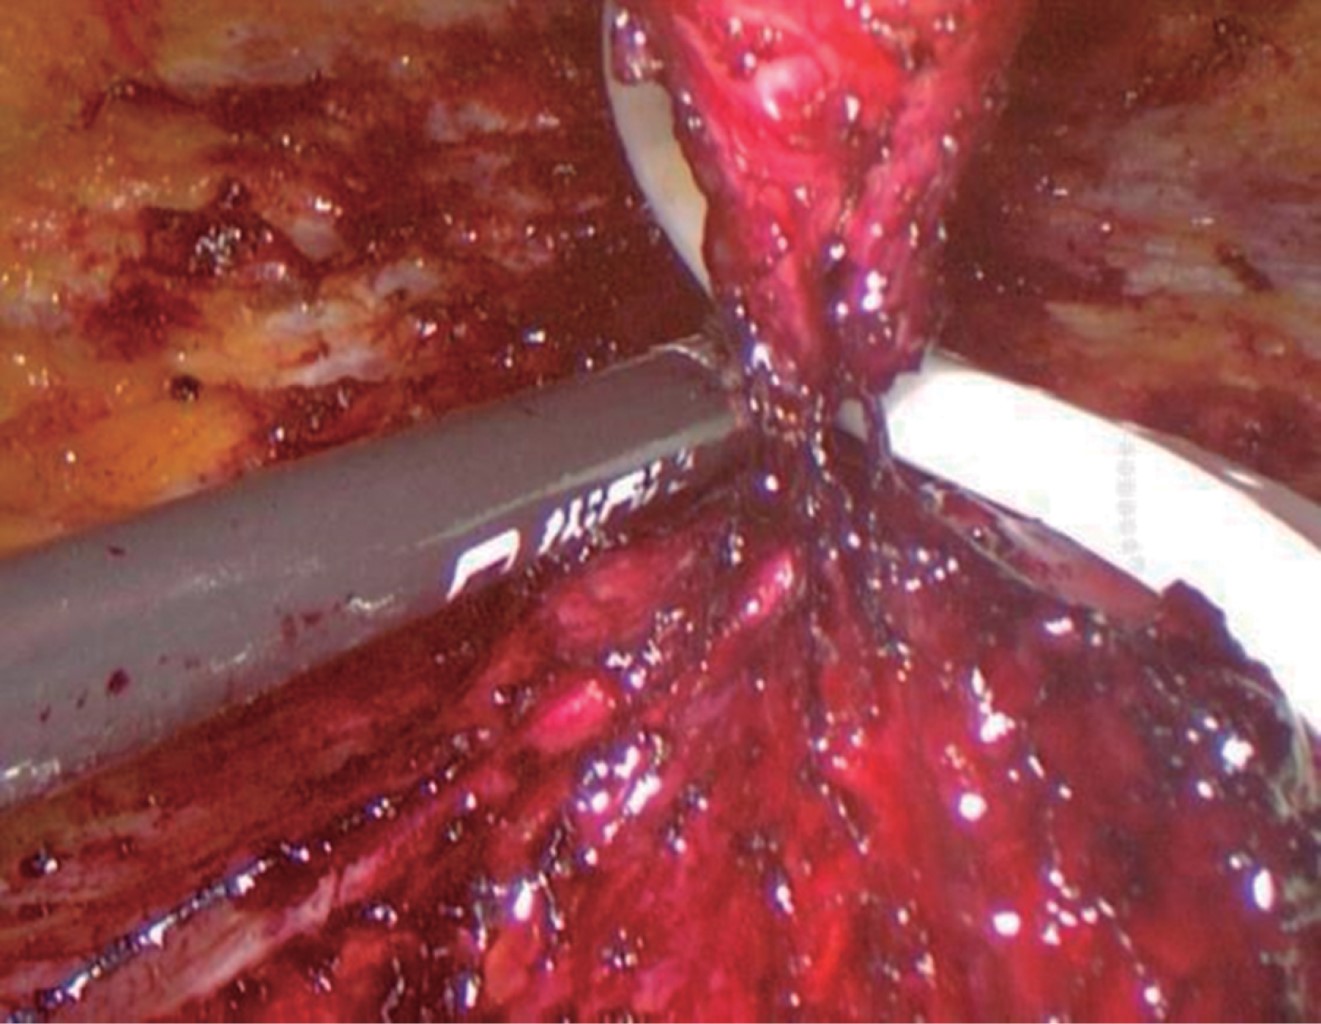

Se coloca al paciente en decúbito dorsal en posición de litotomía extendida bajo efectos de anestesia general. Se marcan los límites hasta dónde se va a extender la disección (Figura 1). Se realiza una incisión transversal de 1.5 a 2 cm por encima del pubis, posteriormente se diseca el tejido subcutáneo hasta la aponeurosis anterior de los rectos abdominales, con disección digital se separa el tejido celular subcutáneo de la aponeurosis hacia superior y lateralmente para crear un espacio ideal en la colocación de un puerto de 11 mm para la óptica por la incisión suprapúbica y dos puertos de trabajo de 5 mm en ambos cuadrantes inferiores (Figura 2). La presión de insuflación de CO2 se mantiene a 8-10 mmHg. Con el uso de tijera armónica, la disección subcutánea se realizó desde la incisión suprapúbica, el ombligo se desinserta la aponeurosis y la disección continua hasta la apófisis xifoides y lateralmente a la línea semilunar (Figura 3). Los defectos son fácilmente identificables, el saco herniario se diseca y el contenido se reduce a la cavidad abdominal (Figura 4). Una vez concluida la disección, se identifica fácilmente la diástasis de los músculos rectos abdominales (Figura 5). Se continúa con la confección de las mallas de acuerdo con el tamaño de los defectos y teniendo en cuenta los principios de reparación de las hernias. Se coloca en el espacio preperitoneal y se cierra el defecto con sutura no absorbible (Figura 4). Se continúa con el marcaje de la diástasis y se procede a la plicatura que debe extenderse desde la apófisis xifoides hasta 2-3 cm por debajo del ombligo. En este caso se usó y se recomienda el uso de suturas barbadas que facilitan la plicatura sin perder la tracción (Figura 5). El ombligo se vuelve a fijar al plano músculo aponeurótico con una o dos suturas simples (Figura 6). Se introduce un drenaje aspirativo para prevenir el seroma y se lo exterioriza por una incisión de 5 mm (Figura 7).

Figura 5